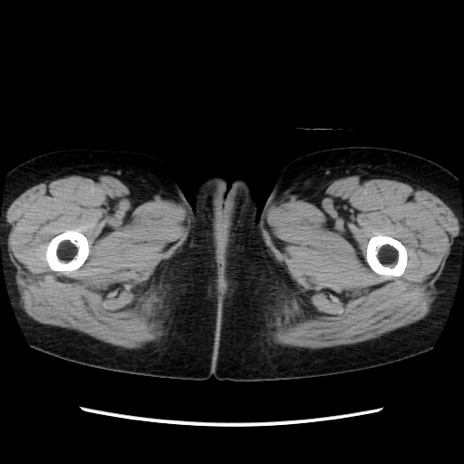

症例32(横断像)

【症例】40歳代 女性

【主訴】上腹部痛、嘔気・嘔吐

【現病歴】約9時間前頃から急に上腹部痛、嘔気、嘔吐が出現。改善しないため救急要請。

【既往歴】子宮頚癌(広汎子宮全摘術、放射線療法)、腸閉塞